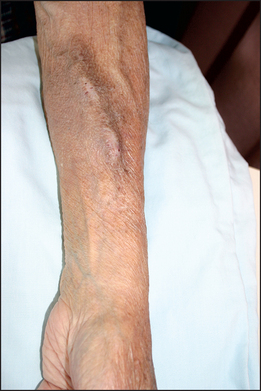

Inspect the patient’s wrists and forearms for scars and palpate for surgically created arteriovenous fistulae or shunts, used for haemodialysis access. There is a longitudinal swelling and a palpable continuous thrill—a characteristic buzzing feel—present over the fistula (see Figure 18.5). There may be scars from previous thrombosed shunts or carpal tunnel syndrome surgery present on either side. Look for signs of the carpal tunnel syndrome.